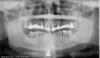

Врач глянул снимок и сказал: Ничего утешительного сказать не могу. Проблема в атрофии(убыли костной ткани) у многих зубов:17,13,27,28,37,36,47.Все они подлежат удалению.В перспективе-либо импланты,либо съёмные протезы.Извините,что не обрадовала ничем.С этим снимком хорошо бы сходить на консультацию к протезисту(а лучше даже к нескольким),послушать независимое мнение.Как вариант-зайдите на сайт stom.ru (на форум),выложите ОПТГ,доктора(в т.ч. и из Москвы) выскажут своё мнение.

Данный снимок не является основой для диагностики. По нему видно, что скорее всего будут удалены все зубы на верхней челюсти , жевательные зубы на нижней челюсти, и есть выраженая дисфункция височнонижнечелюстного сустава.

На данном этапе и по данному снимку возможно только составить корректный план санации и диагностики, которая может занять несколько недель если потребуется перестройка мышечного рефлекса.

провести диагностику, а далее разом убрать все зубы наверху и поставить 6-8 имплантатов и сразу нагрузить временными коронками. Внизу тоже кое-что поудалять придется.